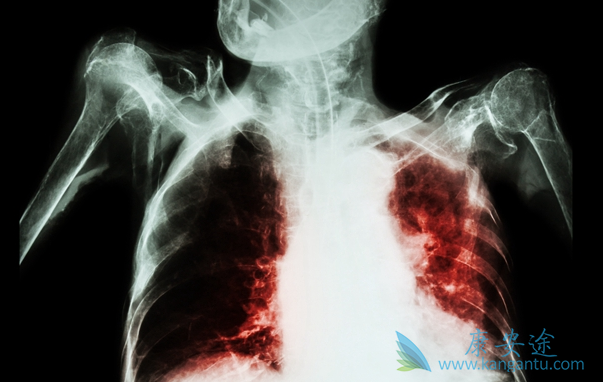

肺癌,是目前全人类的杀手。在我国肺癌是发病率和死亡率双高的恶性肿瘤。从19世纪起,人类陆续开始尝试用手术、放射、化疗等方式来治疗肺癌,但是效果并不理想。大量临床数据表明,肺癌早期的5年生存率高达70%~80%以上,而晚期肺癌的5年生存率为5%以下。随着科学与技术的不断发展,时下,靶向药物、免疫疗法成为新一代的治疗手段深受追捧。那现在肺癌中晚期能治好吗?

对于中晚期肺癌,传统的治疗方法多是化疗联合局部放疗,平均生存期只有1年左右,这也是谈肺癌色变的主要原因。近年来,随着肿瘤分子遗传学的发展,针对肺癌驱动基因和表观遗传学的深入研究,肺癌的靶向治疗、免疫治疗等如火如荼地开展起来了,通过这样的“精准”治疗,中晚期肺癌的5年生存率得到大大提高,肺癌成为“慢性病”的时代即将到来,肺癌的治疗永远在路上,中晚期肺癌并非不可治。

值得关注的是,肺癌是全身性疾病的概念,近年来已逐渐被广大医务工作者所接受。肺癌在原发肿瘤很小时就可以发生远处转移,即使早期肺癌手术切除后也可能出现局部复发和发生远处转移。治疗肺癌不能只着眼于局部治疗,需要外科、内科、放疗科等多学科综合治疗,综合地、科学地、合理地应用现有的局部和全身治疗手段,以期达到临床根治或延长患者生存、改善患者生活质量的目的。